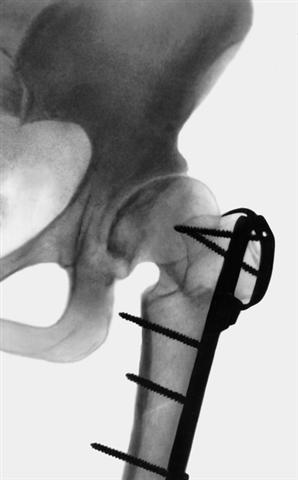

Рис. 3б). Варизирующая остеотомия проксимального конца бедренной кости при коксартрозе: рентгенограмма тазобедренного сустава (прямая проекция) после варизирующей остеотомии.